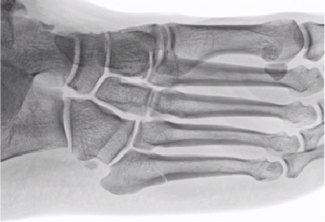

A. Douglas Spitalny, DPM, FACFAS

As a longtime sports fan, I have seen how Jones fractures can alter the success of a season and change the careers of athletes across professional and collegiate sports. The majority do return to their sport, but some do not, with multiple...